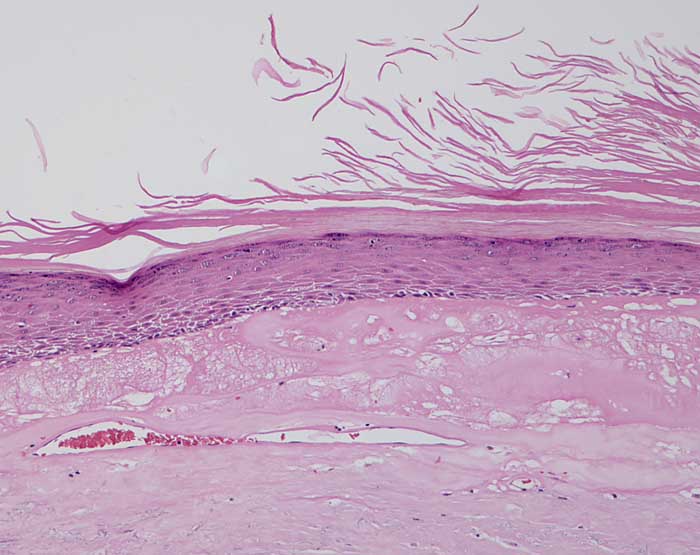

Chronische Radiodermatitis

Hyperkeratose. Zellarme hyalinisierte Dermis. Teleangiektatische Gefässe.

Fraktionierte Bestrahlung vor mehreren Jahren.

Histologie

100